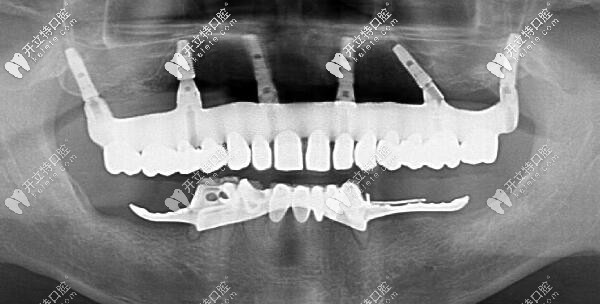

福州維樂ALL-ON-6上半口即刻種植牙后的CT片

ALL-ON-6上半口即刻種植牙后的CT片▲

針對劉先生的缺牙時間長、牙槽骨量不足的情況,陳院長建議用ALL-ON-6數(shù)字化即刻種植技術,用6顆種植體恢復上半口牙,采用3D種植導板精準定位;這樣能縮短手術時間、減少手術創(chuàng)傷和疼痛。

劉先生選擇用價格稍高的瑞典諾貝爾pcc種植體,是因為種植后不容易出現(xiàn)排異、穩(wěn)定性強、使用壽命更長等優(yōu)勢~~

劉先生在福州維樂口腔做ALL-ON-6半口種植牙的整個手術過程差不多用了2個小時,成功植入6顆種植體,手術當天就戴上了臨時牙,回家便可以吃飯啦!